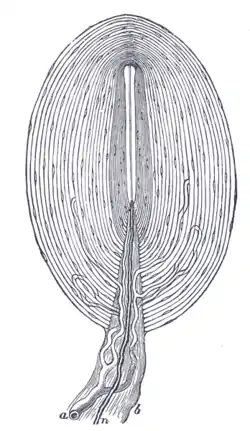

![]() Pacinian corpuscle, with its system of capsules and central cavity. a. Arterial twig, ending in capillaries, which form loops in some of the intercapsular spaces, and one penetrates to the central capsule. b. The fibrous tissue of the stalk. n. Nerve tube advancing to the central capsule, there losing its white matter and stretching along the axis to the opposite end, where it ends by a tuberculated enlargement. | |

The Pacinian corpuscle is approximately oval-cylindrical-shaped and 1 mm in length. The entire corpuscle is wrapped by a layer of connective tissue. Its capsule consists of 20 to 60 concentric lamellae (hence the alternative lamellar corpuscle) including fibroblasts and fibrous connective tissue (mainly Type IV and Type II collagen network), separated by gelatinous material, more than 92% of which is water.[4]